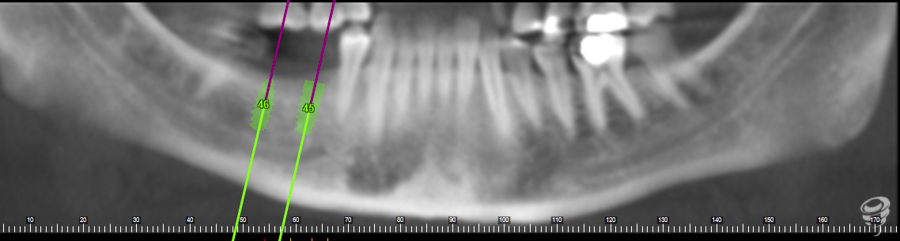

A.M.R Paciente de 40 años de edad, de sexo femenino, edéntula parcial, no fumadora y sin antecedentes médicos de interés. La paciente fue evaluada radiológicamente con una tomografía computarizada de haz cónico y se procedió a la planificación de su caso mediante el sistema informático Galimplant 3D Exacto®. Se planificaron dos implantes galimplant de 4X10mm (IPX 4010).